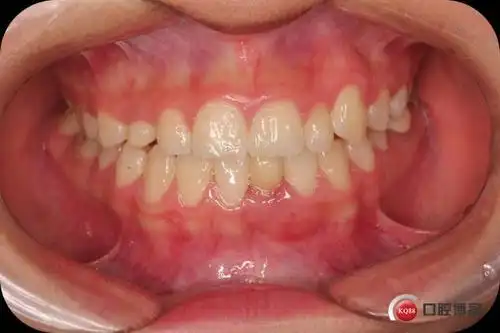

辅助弓矫治一例尖牙错位